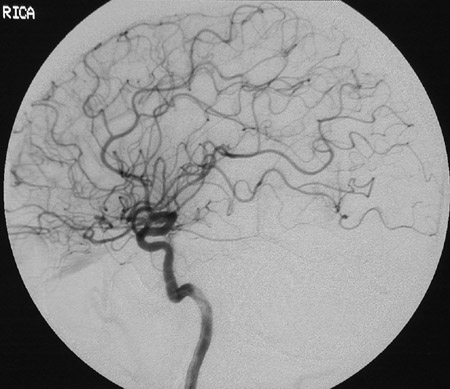

When the doctor started to inject the dye I felt it pass through my neck like a warm trickle. There was a big screen on my left and I tried to move just my eye to check it and I can see the dye travelling through the veins slowly. I held my breath like instructed. Well, it wasn’t that hard. There were 8 more pictures to take and I was praying to God to please make everything okay. Then it was done. They placed a hard ball-like thing on my groin and pressed it hard and held it there for 10 minutes. My back was aching badly and I wanted to stand up but I remembered I can’t. I also wanted to pee. They transferred me to another bed and brought me back to the waiting area where Lay was waiting. My hunger then became a monster but I have never wanted something so badly in my life back then but to drink water. So lay gave me water which I drank through a straw. I watched something on TV but can’t remember exactly what was it. Lay slept on the lazy boy and after a while went to fix the papers. Around 1pm Dr.Rivera arrived to deliver the bad news. He said that there is still another avm seen on the angiogram but this one is tiny and fills very slowly. Upon hearing that I felt like the whole world crashed on me. I was so hopeful. I was praying all the time how could this happen? Isn’t my situation at the moment enough? Do I need to really suffer more? When I heard that I kept a straight face like it didn’t bothered me at all. He said we need to see him in his clinic at the medical arts building after we got discharged in the lab. To explain further. So finally around 3pm we went to his clinic and he explained that what he saw in the angiogram could be an avm which formed after surgery. This was the same explanation given by my neuro surgeon. Because I wondered – how can an avm form in my brain now? When it’s supposed to be congenital or inborn? Arent avms formed during the growth of the embryo in the mother’s womb? Then he explained that since he clipped 3 arteries in my brain with titanium clips of course there wouldn’t be a passage for the blood to pass through so in that case the blood probably took on another route thus the birth of my”new” avm. But wait, there’s good news! Really doc?? The veins fills very slow so the probability that it will burst is lower than my first avm. I just need to be very careful in monitoring my blood pressure. Meaning I can’t get too agitated, need to watch what I eat, etc etc. etc. So I’m a grenade. I can explode any time. Lately I was thinking. Would everything turn out to be futile? Meaning- I’ve been working my ass up in rehab and for what? I’ve been willing myself to get better each day when there is another time bomb ticking somewhere in my temporal lobe. Life is not fair. So if you think you have a difficult life, think again